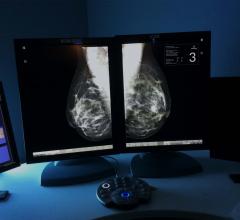

The women’s health channel includes news, videos, podcasts and other content related to technology used to detect and treat breast cancer and cervical cancer, including mammography, breast magnetic resonance imaging (MRI), automated breast ultrasound (ABUS), breast ultrasound, breast biopsy and breast radiation therapy.